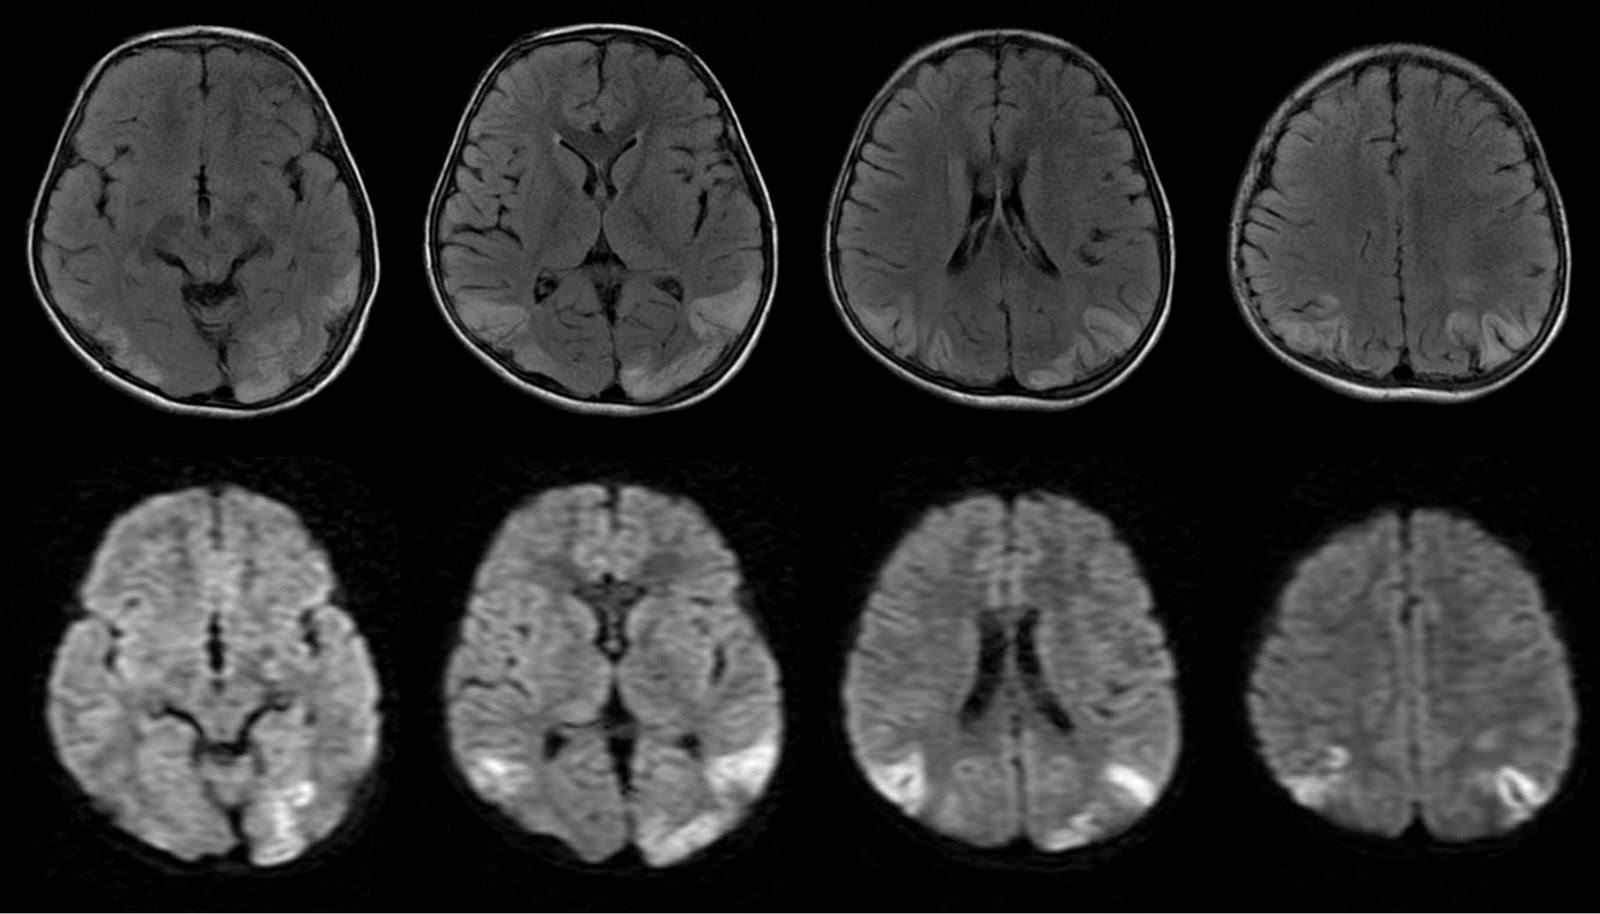

Chẩn đoán hình ảnh: MRI não nên được thực hiện một cách hệ thống khi nghi ngờ viêm não sau nhiễm trùng. MRI là phương pháp chẩn đoán hình ảnh nhạy nhất để phát hiện các dấu hiệu phù hợp với viêm não do HSV, chẳng hạn như sự liên quan của thùy thái dương và trán. CT có thể cho thấy các tổn thương giảm mật độ ở thùy thái dương khi có sự liên quan của HSV, thường xuất hiện 3-5 ngày sau nhiễm trùng.